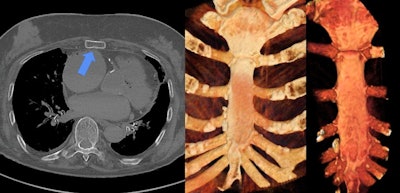

Once referred to as "3D on steroids," cinematic rendering (CR) has now become a powerful and effective tool to present pathologies found in postmortem CT for judicial reviews. That's the view of German researchers who have evaluated over 100 fractures and soft-tissue injuries.

"When we first tested cinematic rendering in 2017, we immediately saw the huge difference between it and the classic volume rendering (VR) technique, with CR creating more vivid, photorealistic reconstructions," Judith Böven, scientific associate at the department of diagnostic and interventional radiology, Düsseldorf University Hospital, told AuntMinnieEurope.com.

Between February 2016 and March 2019, Böven and her colleagues analyzed 112 fractures and injuries from 33 human cadavers (8 women, 25 men, with a mean age of 54 ± 18 years, range 31-92 years) that underwent whole-body postmortem CT after traumatic death. They reconstructed pathologies with CR and VR techniques, and classified fractures according to their dislocation.

CR was more expressive than VR for all three trauma categories (p < 0.01). Also, CR was more expressive than conventional CT when used for fractures with dislocation (p < 0.001), injuries of the ventral body surface (p < 0.001), and demonstration of foreign bodies (p = 0.033). CR and VR became more expressive with a higher grade of fracture dislocation (p < 0.001). In total, 20% of all pathologies in the CR and VR reconstructions were not detectable by radiologists.

"CT showed the same evaluation for expressiveness given by forensic pathologists in every grade of dislocation, whereas a strong correlation between grade of dislocation for fractures and CR expressiveness was found, as well as for VR reconstruction images," the authors wrote. "Reconstructions of fractures with major dislocation were declared useful for forensic reports in 84% of the cases."